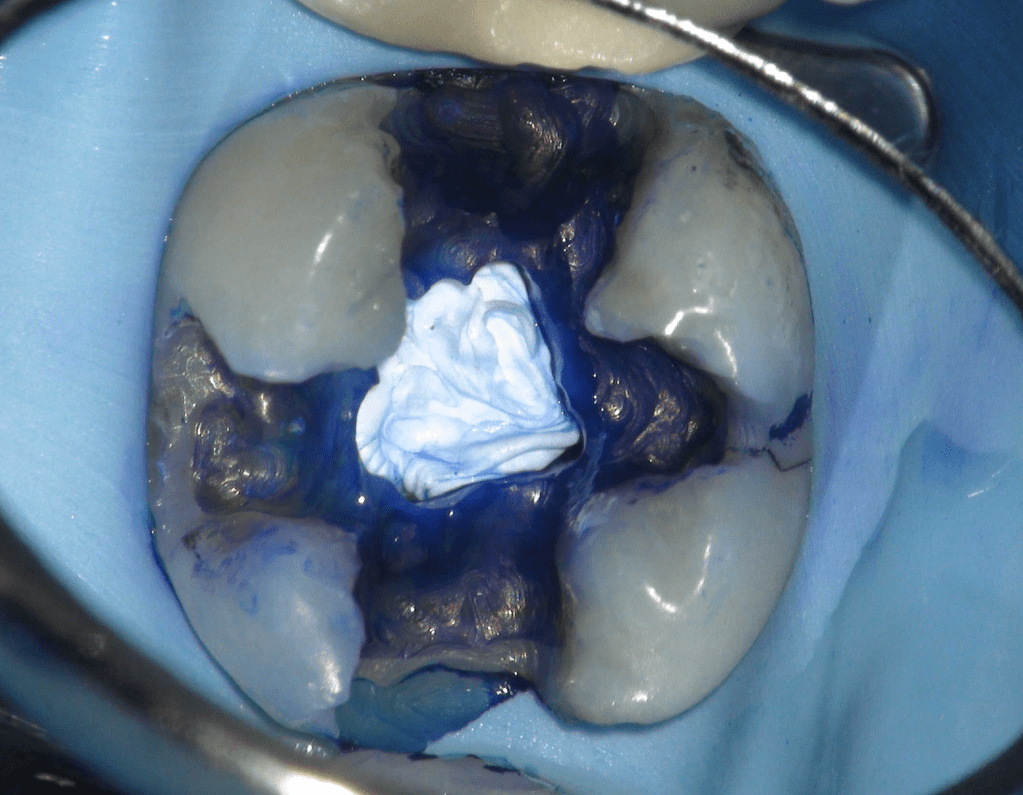

Pulpotomía biodentine + reco preendio